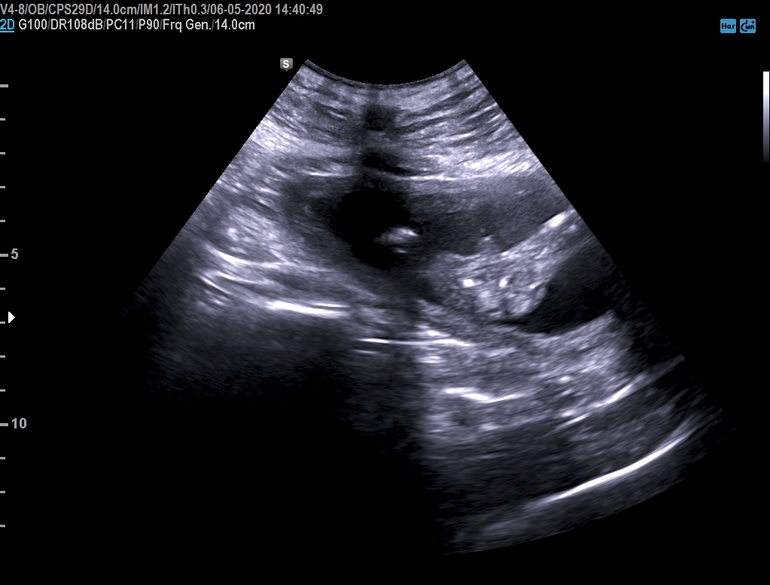

Анна Бернецкая

Девочки если вам не трудно, можете покидать фото с ваших узи , уж очень интересно для сравнения 🤨

мой мальчишка, срок 17+4